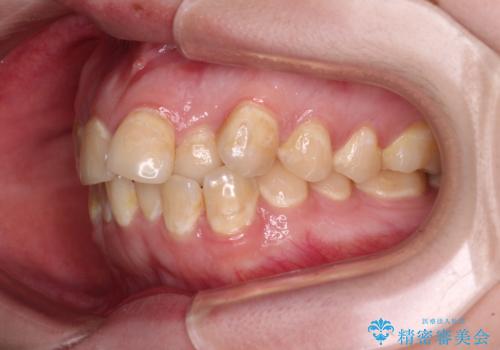

- 前歯のデコボコとクロスバイトが気になり、インビザラインによる矯正治療を希望して来院された患者様です。

上顎側切歯(上の真ん中から2番目の歯)が舌側転位している場合、無理して動かそうとすると歯髄壊死を起こすリスクが高い印象があります。

インビザライン単体でも治療は可能ですが、安全策としてインビザラインで歯列を移動する前に上顎前歯をワイヤー矯正で整え、その後上下歯列をインビザラインにて矯正治療を行うこととしました。

舌側転位している側切歯特有の、切縁の位置が不揃いであったり、根元が内側に引っ込んだ状態であったりという、インビザライン独特の仕上がりになることなく、きれいに整った歯列とすることができました。